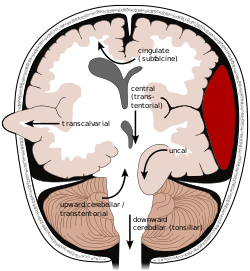

Classification

The tentorium is an extension of the dura mater that separates the cerebellum from the cerebrum. There are two major classes of herniation: supratentorial and infratentorial. Supratentorial herniation is of structures normally above the tentorial notch and infratentorial is of structures normally below it.[4]

- Supratentorial herniation

- Uncal (transtentorial)

- Central

- Cingulate (subfalcine/transfalcine)

- Transcalvarial

- Tectal (posterior)

- Infratentorial herniation

- Upward (upward cerebellar or upward transtentorial)

- Tonsillar (downward cerebellar)